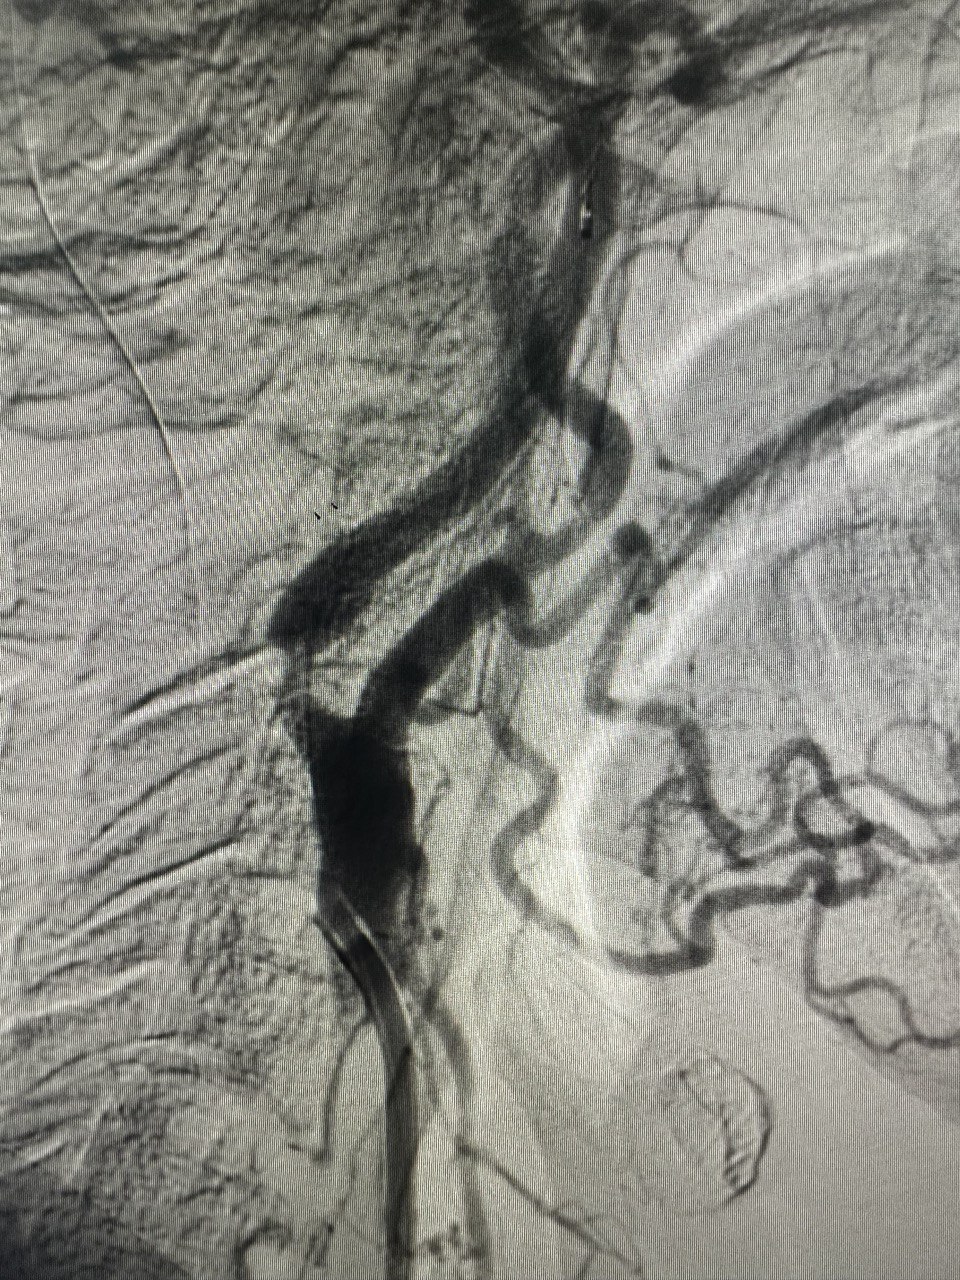

Стентування сонних артерій (CAS) – це процедура, яка виконується для відкриття звуженої сонної артерії. Вона полягає і розміщенні стенту (сітчаста трубка) в звужену артерію. Ця процедура також називається каротидною ангіопластикою.

Є дві сонні артерії (по одній з кожного боку шиї), які кровопостачають мозок. Ці артерії можуть бути звужені та пошкоджені жировими відкладеннями (атеросклеротичними бляшками). Ця бляшка може обмежити приплив крові до мозку, що підвищує ризик інсульту.

Стеноз сонної артерії до та після стентування

Як виконується стентування сонних артерій

Під час стентування сонної артерії в сонну артерію вставляється стент (невелика сітчаста трубка, що розширює артерію зсередини).

Для введення стенту лікар використовує іншу трубку, яка називається катетером. Лікар вводить катетер у кровоносну судину в паху чи зап’ясті і переміщає його до сонної артерії.

Усередині катетера знаходиться дуже тонкий провідник. Провідник використовується для переміщення балона та стента в сонну артерію. Балон поміщають усередину стенту і надувають. Це відкриває стент та притискає його до стінок артерії. Потім балон здувають та видаляють, залишаючи стент на місці.